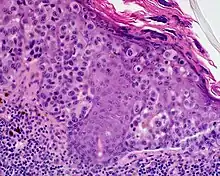

Lentigo maligna melanoma is a melanoma that has evolved from a lentigo maligna,[1]:695 as seen as a lentigo maligna with melanoma cells invading below the boundaries of the epidermis.[2] They are usually found on chronically sun damaged skin such as the face and the forearms of the elderly.

An invasive tumor arising from a classical lentigo maligna. Usually a darkly pigmented raised papule or nodule, arising from a patch of irregularly pigmented flat brown to dark brown lesion of sun exposed skin of the face or arms in an elderly patient.